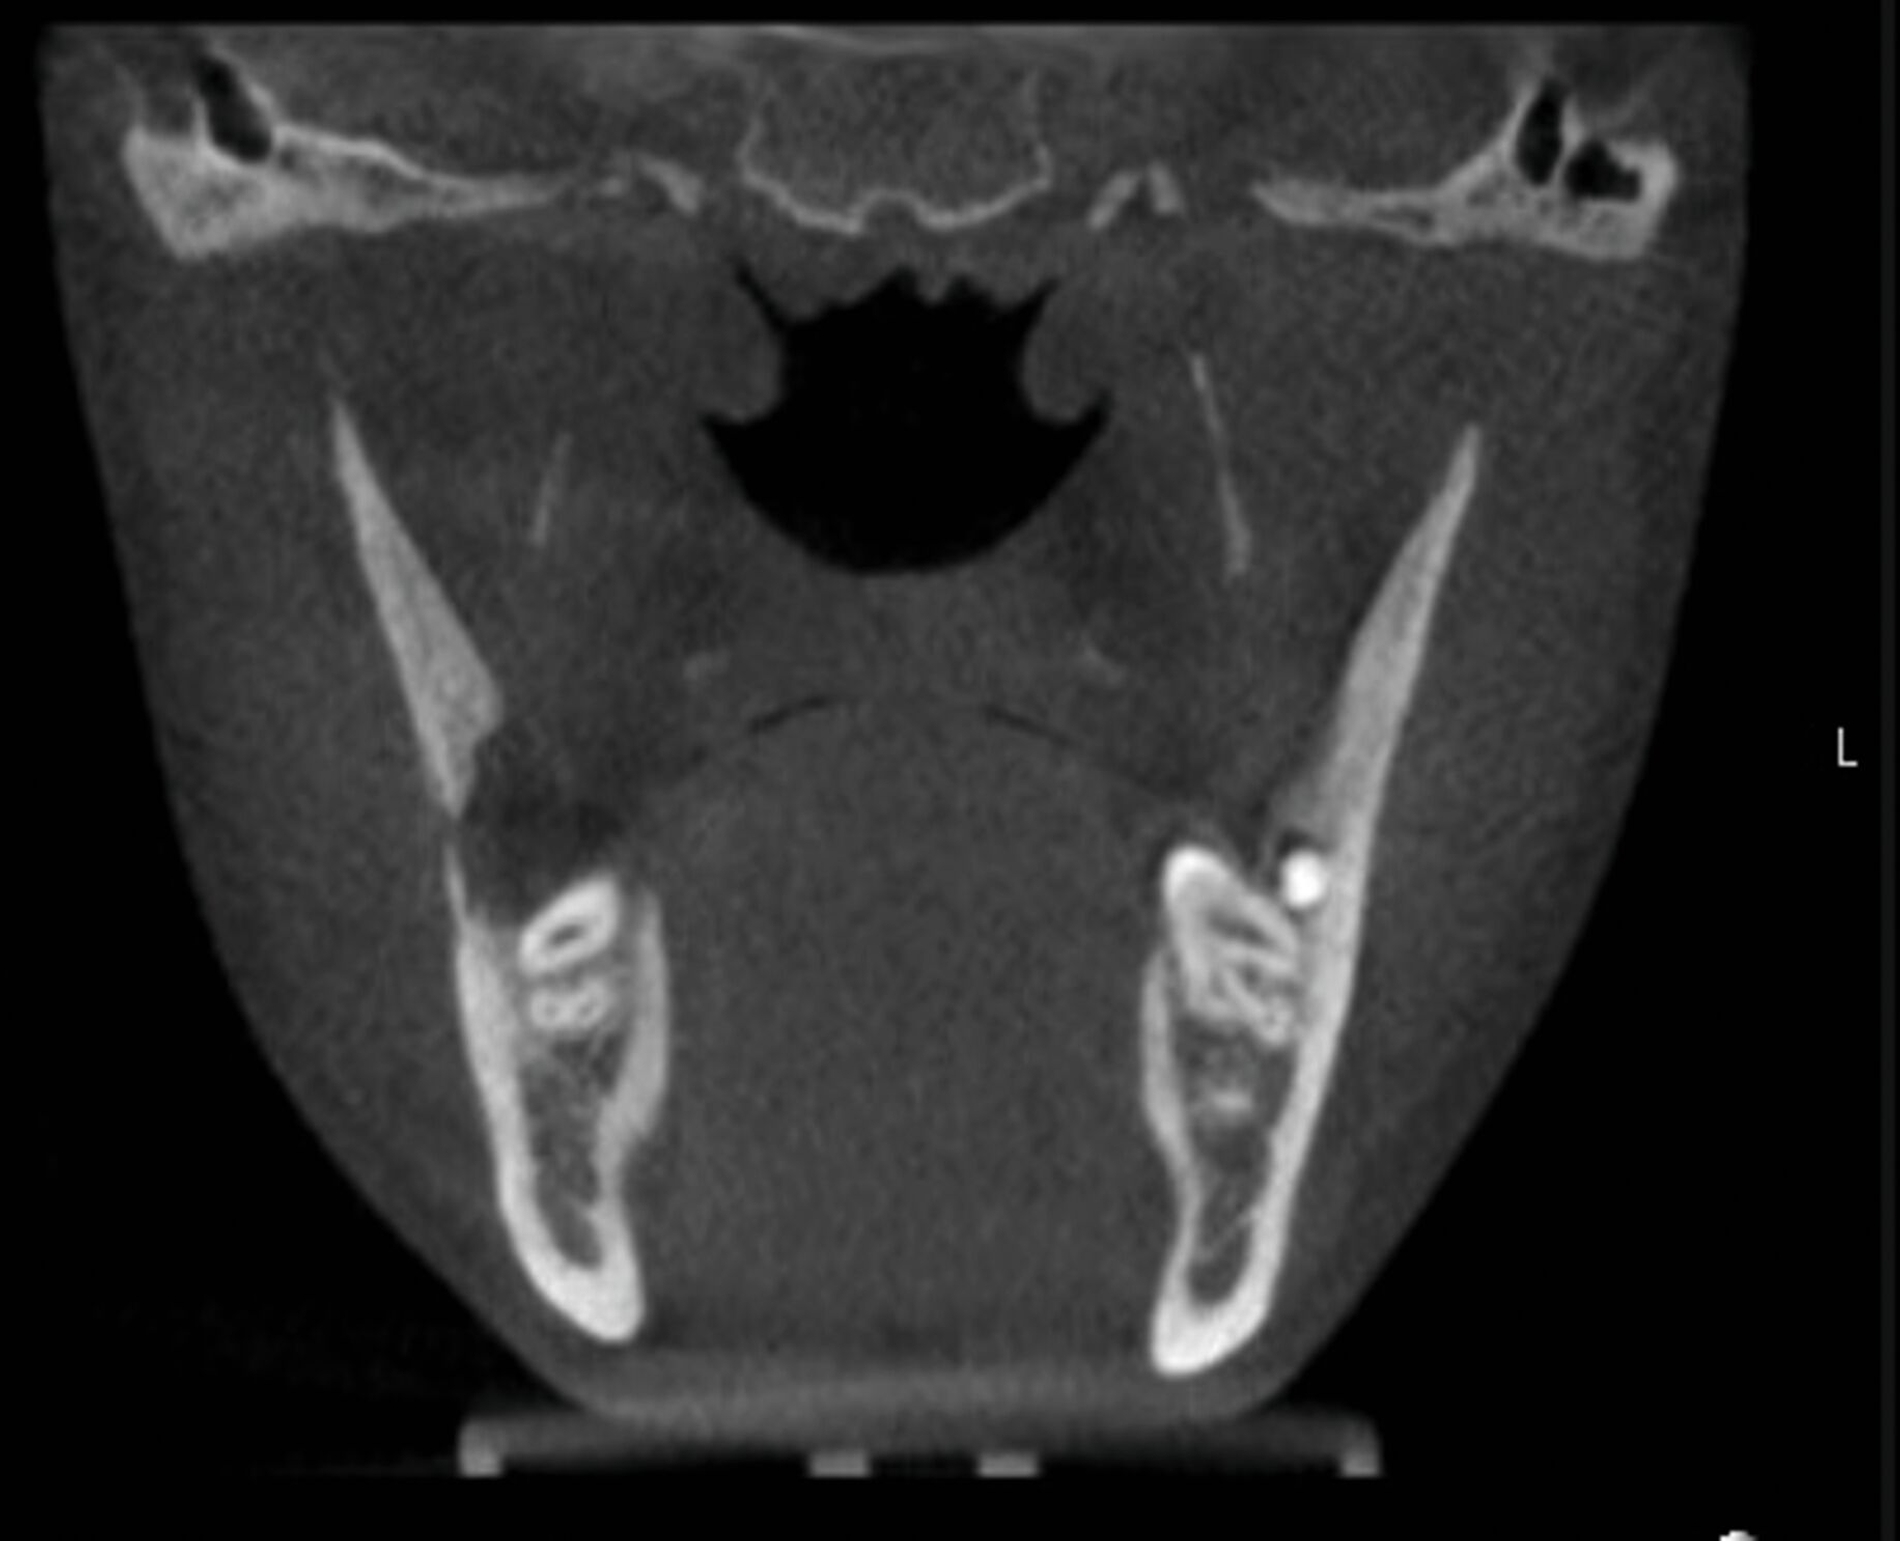

Dieser Patient stellte sich nun mit Schmerzen und Druckdolenz im Kieferwinkel rechts vor. Der enorale Befund zeigte weder eine Fehlokklusion noch ein Os liberum, die faziale Sensomotorik war seitengleich intakt. Die allgemeine Anamnese förderte jedoch eine Osteogenesis imperfecta Typ I zutage („Glasknochenkrankheit“). Das ad domo angefertigte DVT ergab den Befund einer Fraktur an der Linea obliqua rechts (Abbildung 2).

Nach ausführlicher Besprechung der Diagnose und der Therapieoptionen erfolgte am nächsten Tag die Reposition und Osteosynthese in Intubationsnarkose. Dabei konnte die Fraktur reponiert und mittels 6-Loch-Platte nach Champy stabilisiert werden (Abbildung 3). Der Patient konnte bei regelhafter postoperativer radiologischer Kontrolle am dritten postoperativen Tag in die ambulante Nachsorge entlassen werden.